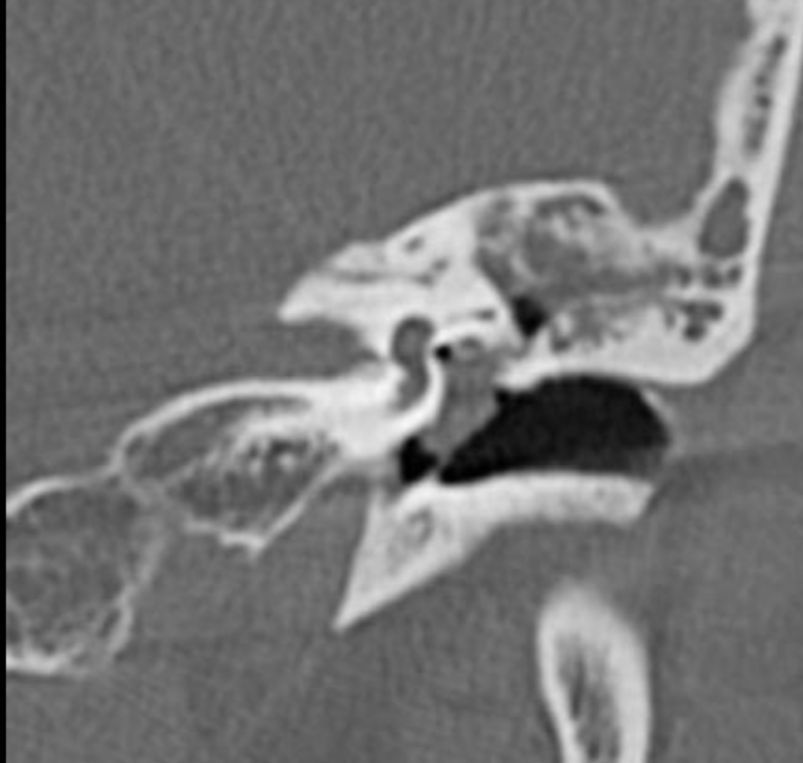

¿Cuáles son las pistas diagnósticas en la TC de la otitis media?

¿Cuáles son los hallazgos radiológicos en la TC de mastoiditis?

El colesteatoma destruye:

¿Cuál es una pista característica del colesteatoma?

Destruye hueso